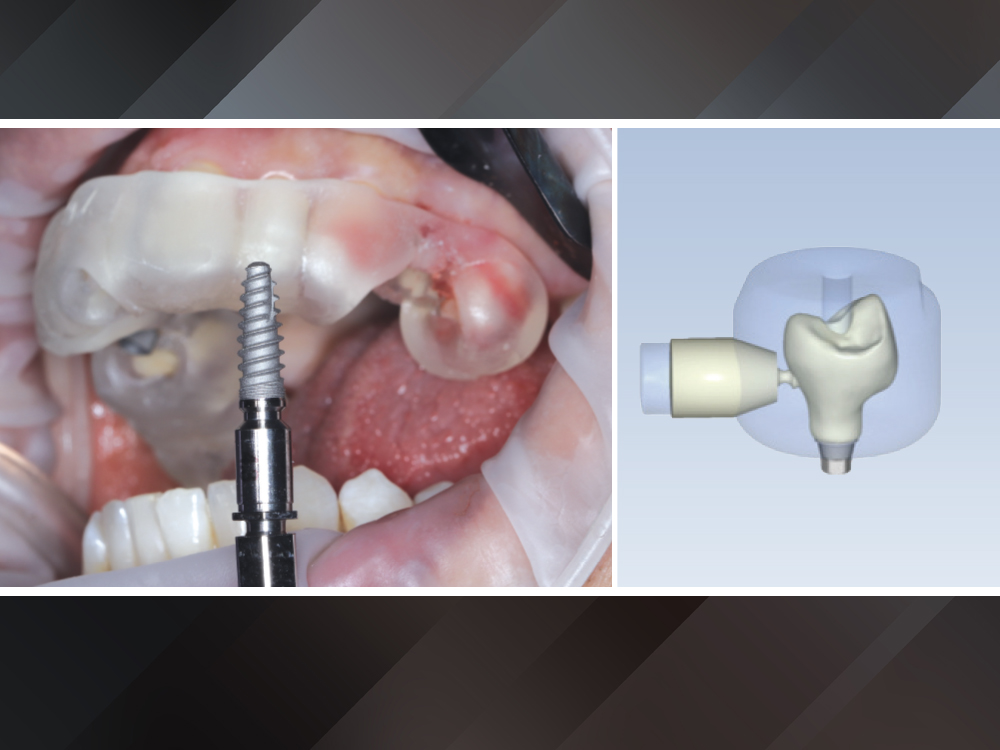

Surgery was performed under local anesthesia with the printed guide securely seated for full control of angulation and depth

Two Glidewell HT™ Implants (Glidewell Direct; Irvine, Calif.) were placed according to the digital plan, achieving excellent primary stability-b

Two Glidewell HT™ Implants (Glidewell Direct; Irvine, Calif.) were placed according to the digital plan, achieving excellent primary stability-c

Figures 4a–4c: Surgery was performed under local anesthesia with the printed guide securely seated for full control of angulation and depth. Two Glidewell HT™ Implants (Glidewell Direct; Irvine, Calif.) were placed according to the digital plan, achieving excellent primary stability.